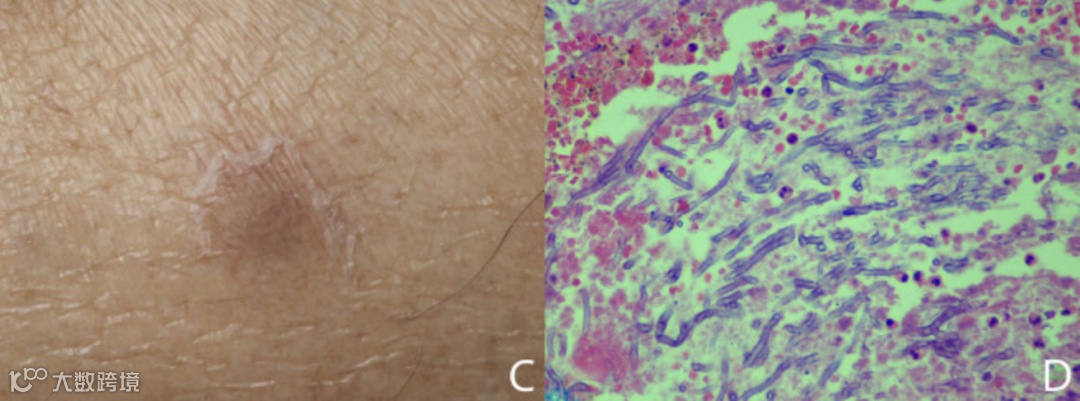

尽管进行了治疗,患者在右小腿出现了疼痛的黑色隆起性丘疹(图C)。皮肤切开活检发现化脓性肉芽肿性炎症和真菌菌丝(图D),皮肤组织培养呈黄曲霉菌阳性。停止使用伏立康唑,并开始为期2周的卡泊芬净70mg静脉注射,每日一次。外周血、痰和中心静脉导管的真菌培养阴性,超声未见血管赘生物。患者的病情持续恶化,再次培养确诊鲍曼不动杆菌肺炎,使用厄他培南治疗。患者在移植后第80天死亡。尸检死因为曲霉病和终末期肾衰竭导致的多器官衰竭。